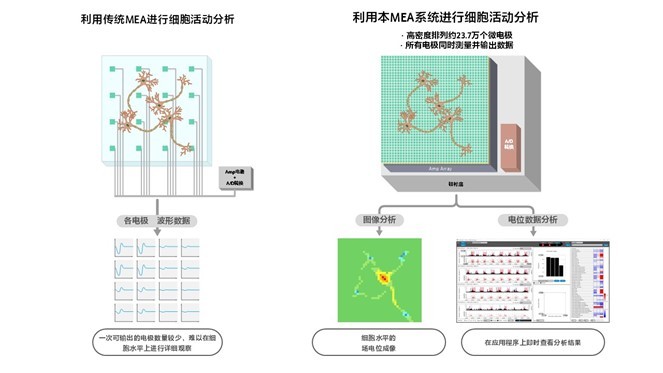

此次三家公司携手日本东北工业大学(下称“东北工大”)新开发的高密度MEA系统,可基于细胞电活动数据,在单细胞水平上比对和监测病态细胞和健康细胞的差异以及细胞对化合物的反应。具体而言,该系统通过整合索尼正在开发的高密度CMOS-MEA与SCREEN集团的细胞电活动测量技术,利用高密度排列的微电极检测细胞外电位,并输出图像数据。这使得用户能够在观测细胞放电*2的同时,精准测量与记录细胞反应。此外,该系统还集成了在索尼和东北工大的联合研究成果所构建的基础框架,搭载由VitroVo专为化合物评估优化的算法,以及具备友好操作界面的数据分析应用程序。由此,细胞放电频率等分析结果可基于电位与图像数据实时显示。该系统的测量与分析功能不仅能获取比传统MEA系统更高密度的细胞活动数据,还可捕捉以往难以观测的实验现象。

・ CMOS-MEA是一种可以实时观测细胞电活动的设备。在传感器芯片上高密度集成了的微电极阵列(Microelectrode Array; MEA),能够捕捉细胞活动过程中的离子流入流出产生的电位变化,经信号处理后输出图像数据。用户可以通过图像直观查看药物等化合物对细胞的影响以及细胞之间的信息传递过程。

・ 索尼正在开发的CMOS-MEA通过缩小电极间距,在保持紧凑体积的前提下,实现单个芯片高密度集成约23.7万个电极。同时,依托索尼在图像传感器开发过程中积累的高速A/D转换技术和高速接口技术,本系统可以实现对大规模电极数据的同步读取。

・ 索尼和东北工大的联合研究证实,CMOS-MEA可以突破传统技术限制,实现基于图像的细胞高清监测和单细胞级数据分析。